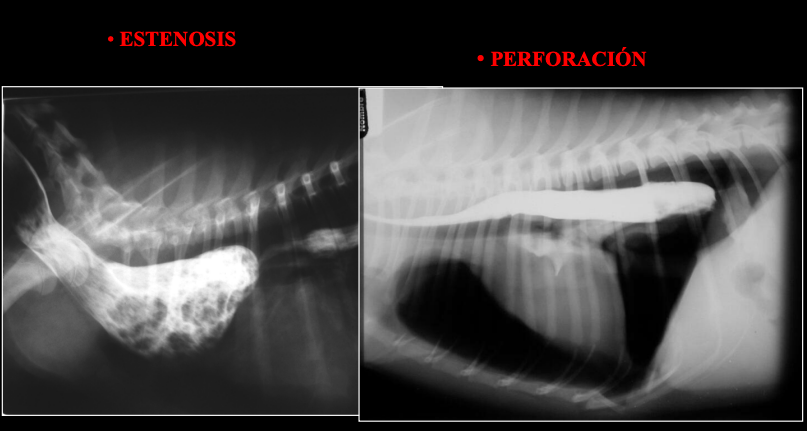

ESOFAGOGRAFÍA POSITIVA

Patologías:

- Megaesófago

- Divertículo esofágico

- Estenosis: Estrechez, estrechamiento de un orificio o conducto. que no esteatosis

- Perforación

- Masas esofágicas

- Enfermedades de hiato